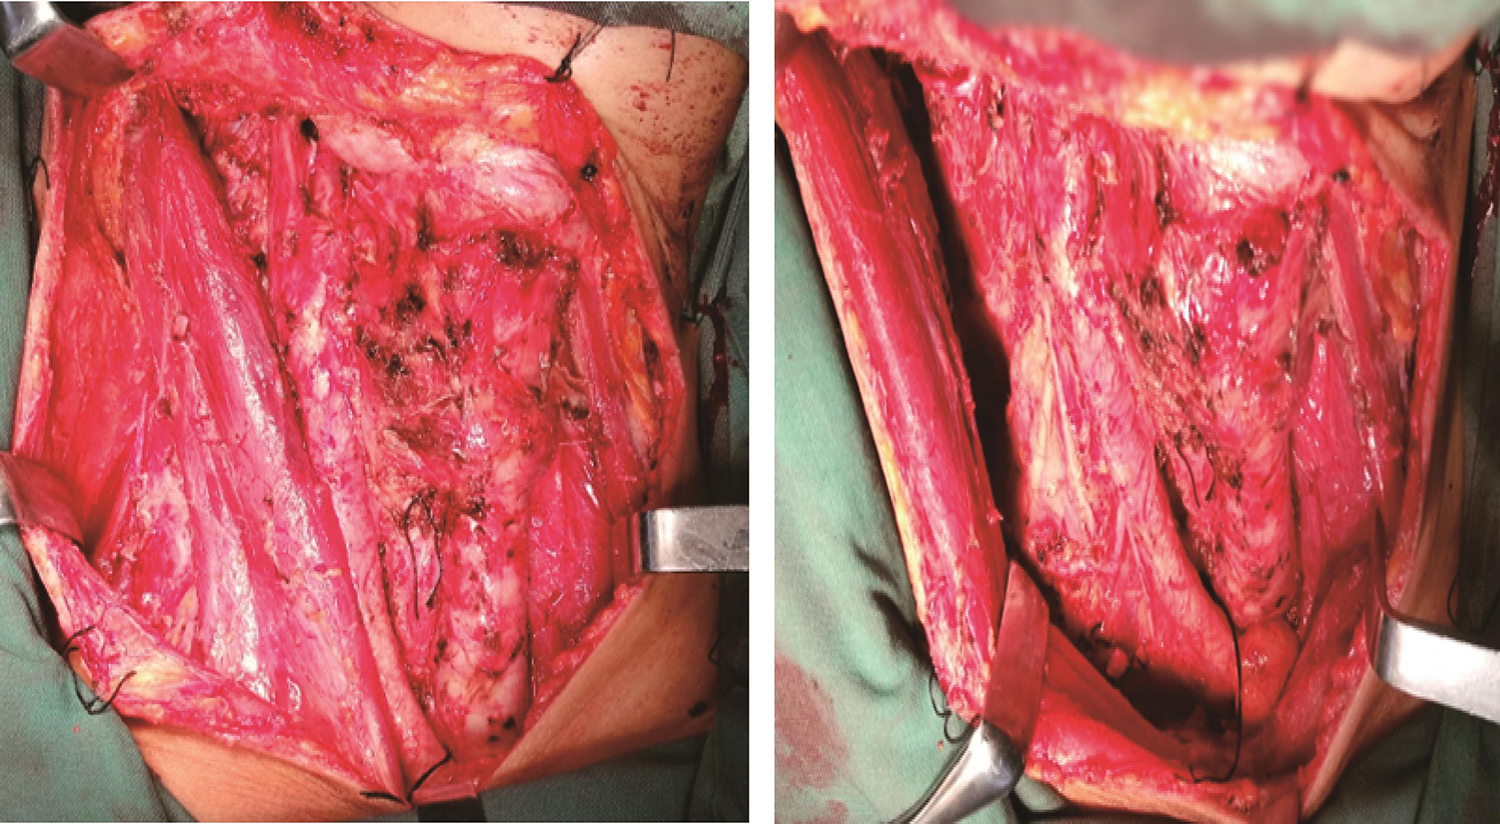

距颈前肿块周约1.5cm做一类梭形切口(图7),切开皮肤、皮下组织及颈阔肌,分离皮瓣。先行右颈清扫,切除受累的颈内静脉,保留胸锁乳突肌、副神经。于胸骨上窝显露右侧带状肌下端并切断,显露甲状腺左叶及左侧喉返神经,保留左上甲状旁腺,完成甲状腺左叶切除及左侧Ⅵ区清扫后(图8),将标本(右颈清扫组织)沿右侧颈总动脉表面分离,显露右侧喉返神经,见肿瘤包绕侵袭神经,遂切除受累的喉返神经,将甲状腺右叶、右侧Ⅵ区淋巴脂肪组织、受累的右侧带状肌、皮肤一同自气管表面切除(图9)。标本包括:全甲状腺、双侧Ⅵ区与右颈清扫组织、受累的颈前皮肤及带状肌(图10)。冲洗术腔后,取耳大神经,长度约5cm,并标记其近心端及远心端,显微镜下行右侧喉返神经移植:修剪耳大神经及喉返神经的断端,采用神经外膜缝合法,用8-0的PROLENE将耳大神经与喉返神经的近心端间断对位缝合4针,同法行神经的远心端吻合,检查已吻合的神经无张力及扭曲(图11)。放置引流管后,拉拢缝合切口。

图8 甲状腺左叶切除及左侧颈部Ⅵ区清扫后

图9 甲状腺右叶、右侧颈部Ⅵ区淋巴脂肪组织、受累的右侧带状肌、皮肤一并切除后